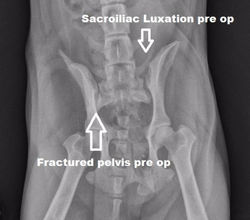

![]() FEMUR FRACTURE | ![]() PLATE FEMUR | ![]() FRACTURE PELVIS/ SI LUXATION |